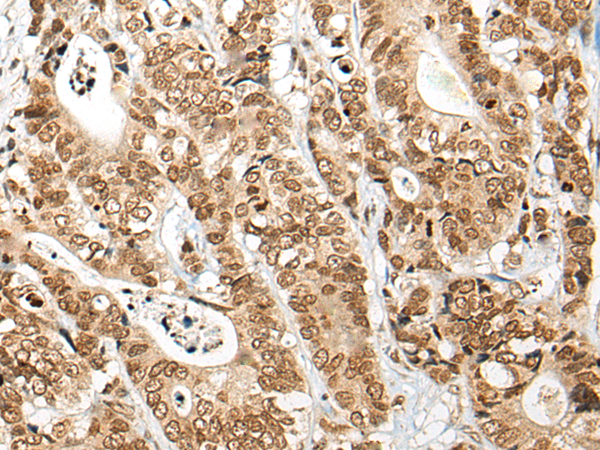

IHC positive control: |

Human thyroid cancer and human esophagus cancer |